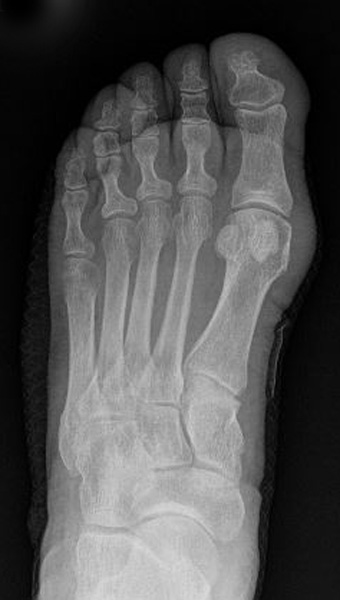

Abb. 12b: Dorsoplantare Röntgenkontrolle nach medial schließender Osteotomie mit Schraubenosteosynthese.

Abb. 12c: Schrägaufnahme nach medial schließender Osteotomie mit Schraubenosteosynthese.

Abb. 12d: Seitliche Aufnahme nach medial schließender Osteotomie mit Schraubenosteosynthese.